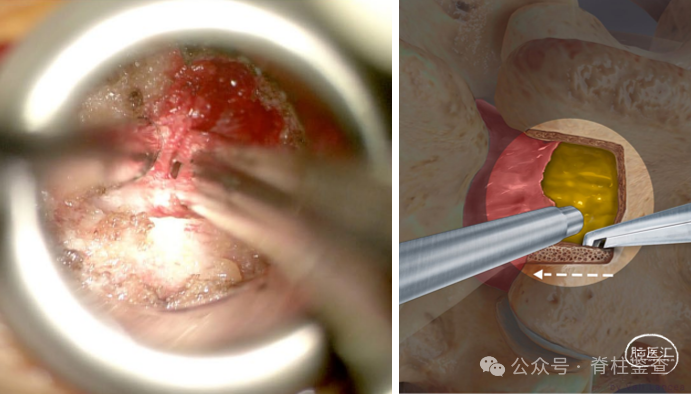

磨钻磨除椎板,从椎板缺损边缘向上延伸以远离瘢痕。

也可利用神经探钩创建瘢痕和小关节平面,进行小关节切除。(小关节的尾部,疤痕附着在硬膜和神经根上,硬膜撕裂的风险最高)